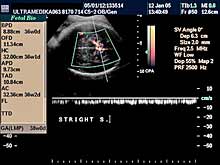

C) III trimestar trudnoće

od 24. do 40. nedelje trudnoće

Indikacija za ultrazvučni pregled:

- Procena funkcije bubrega, organa abdomena, srca i cirkulacije likvora

u mozgu.

Napomena: Na svakom pregledu do kraja trudnoće.

- Procena relativnih i organskih suženja sabirnog sistema bubrega i

izvodnih kanala bubrega i mokraćne bešike.

Napomena: Obavezna primena

3D Sono CT i XRes.

- Procena eventualnih suženja izvodnih traktova srca ploda.

Napomena:

Primena Broadband - CD ili CPA i 3D CPA.

- Stalna procena ehostrukture organa ploda i njegov ukupni porast.

Napomena: Kod "hiperehogenih bubrega" procena renalnih aretrija CPD.

Stalna procena volumena pluća, želudca i veličine creva.

- Procena bolesti histiogeneze mozga ploda od 26 nedelje gestacije.

Napomena: Procena moždane cirkulacije Broadband - CD i CPA i/ili 3DCPA.

- Procena izostanka treće faze embriogeneze mozga

OD 26 NEDELJE DO KRAJA

TRUDNOĆE.

- Registrovanje destruktivnih lezija mozga fetusa.

Napomena: Mogu

nastati krvarenja mozga zbog nedostatka vitamina K (hemoragija

intrakranijalis - HIC), hipoksično-ishemične promene koje dovode do

periventrikularne i subkortikalne leukomalacije - PVL i SCL.

- Registrovanje pojave tumora organa ploda i otkrivanje infekcija ploda.

Napomena: Mada su tumori ploda retki, obično se registruju u drugoj

polovini trudnoće. Njihova tačna i blagovremena dijagnoza je u većini

slučajeva ključna u lečenju deteta.

- Od 28. nedelje procena spuštenosti testisa.

Napomena: Ova informacija

je ključna za lečenje u slučaju izostanka dospevanja testisa u skrotume u toku trudnoće.

- Procena funkcije žučnih i pankreasnih puteva.

Napomena: Blagovremena

dijagnoza omogućava i hitnu odluku o hirurškom lečenju bebe,

neposredno nakon rođenja.

- Od 34. nedelje gestacije procena epifiza kolenih zglobova. Napomena:

Ključna informacija u slučaju postojanja bolesti štitne žlezde ploda

koja je praćena zastojem razvoja inteligencije nakon rađanja bebe.

- U slučaju zastoja porasta ploda procena redistribucije krvotoka i

određivanja termina porođaja.

Napomena: Tačnost je zasnovana na

primeni Broadband Color Dopplera i Color Power Dopplera.

- Procena posteljice i protoka pupčanika, kao i njegov tok i položaj.

Napomena: mogućnost pogrešnog položaja pupčanika na posteljici,

njegovo prednjačenje u porođaju, ili njegov neadekvatan položaj oko

dela tela ploda, ili formiranje čvora ili zapušenje, su krucijalna

informacija u toku pregleda do tada normalne trudnoće.

- U 37. nedelji trudnoće procena veličine grlića endovaginalnom sondom.

Napomena: Dužina i izgled grlića mogu pouzdano odrediti termin carskog

reza i očekivanog porođaja, i mogućnosti ili ne mogućnost završetka

porođaja indukcijom.

|

U III trimestru pregled trudnoće zbog velikog broja

indikacija treba nastaviti u 4 nedeljnim intervalima. Nekad se donosi

odluka o ranijem terminu porođaja, hitnom carskom rezu, a izuzetno

retko o prekidu trudnoće na osnovu podataka dobijenih u toku redovne

ultrazvučne kontrole trudnoće u III trimestru.